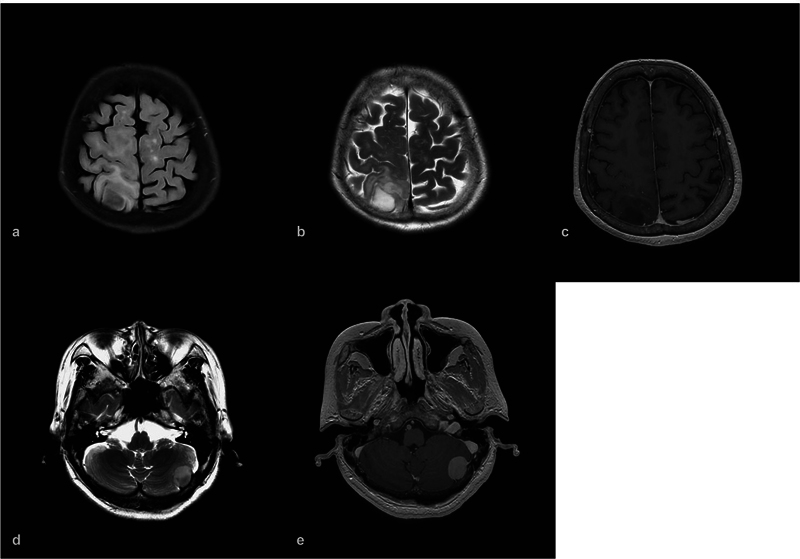

胶质瘤和脑膜瘤是两种常见的原发性脑肿瘤,但在同一患者中同时发生是罕见的。作者想报告一例共存的上顶叶弥漫性胶质瘤,idh野生型,组织学中枢神经系统WHO分级3级和左后窝移行性脑膜瘤,WHO分级1级;在一次手术中成功切除了两个肿瘤。一名68岁女性高血压患者向我们就诊,主诉为左下肢不自主震颤并伴有左上肢刺痛、头晕和颈部酸痛。她被发现在她的右顶叶区有一个病变,在她的左小脑区有一个肿瘤。在与患者详细讨论和全面的术前评估后,作者在一期手术中进行了右侧顶骨开颅和左侧乙状结肠后入路切除这两个肿瘤,证明这两个肿瘤具有两种不同的组织学特征。结论两个相距较远的肿瘤的治疗需要具体情况具体分析。在处理此类病例时,一个重要的方面是决定哪个肿瘤需要先手术,或者两个病变是否可以一次手术同时手术。

Introduction  Gliomas and meningiomas are two common primary brain tumors, but occurring simultaneously in the same patient is a rare entity. The authors would like to report a case of coexistence of a superior parietal lobule diffuse glioma, IDH-wild type, histologically CNS WHO grade 3 and a left posterior fossa transitional meningioma, WHO grade 1; both the tumors were successfully removed in one-stage operation. Case Presentation  A 68-year-old female having hypertension, who presented to us with the chief complaints of involuntary shaking of her left lower limb associated with her left upper limb tingle, dizziness, and neck soreness. She was found to have a lesion in her right parietal region and a tumor in her left cerebellar region. After detailed discussion with the patient and thorough preoperative evaluation, the authors performed a right parietal craniotomy and a left retrosigmoid approach in one-stage operation to remove both the tumors, which were proven to be of two distinct histological identities. Conclusion  The management for two tumors located far apart needs a case-by-case evaluation. An important aspect while dealing with such cases is to decide which tumor needs to be operated first or whether both lesions can be operated at the same time with one-stage operation.